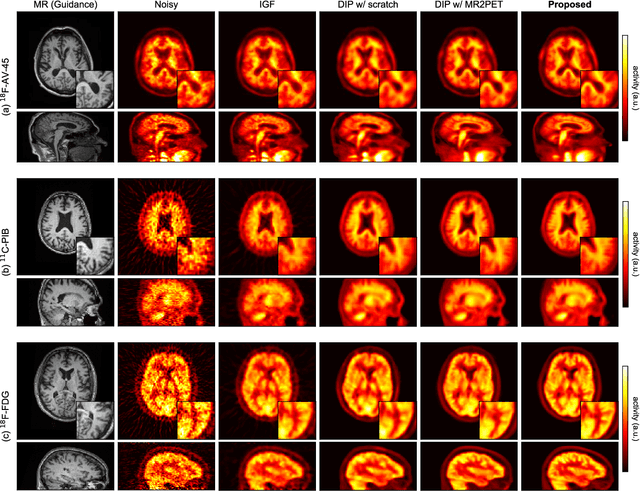

Abstract:Deep image prior (DIP) has been successfully applied to positron emission tomography (PET) image restoration, enabling represent implicit prior using only convolutional neural network architecture without training dataset, whereas the general supervised approach requires massive low- and high-quality PET image pairs. To answer the increased need for PET imaging with DIP, it is indispensable to improve the performance of the underlying DIP itself. Here, we propose a self-supervised pre-training model to improve the DIP-based PET image denoising performance. Our proposed pre-training model acquires transferable and generalizable visual representations from only unlabeled PET images by restoring various degraded PET images in a self-supervised approach. We evaluated the proposed method using clinical brain PET data with various radioactive tracers ($^{18}$F-florbetapir, $^{11}$C-Pittsburgh compound-B, $^{18}$F-fluoro-2-deoxy-D-glucose, and $^{15}$O-CO$_{2}$) acquired from different PET scanners. The proposed method using the self-supervised pre-training model achieved robust and state-of-the-art denoising performance while retaining spatial details and quantification accuracy compared to other unsupervised methods and pre-training model. These results highlight the potential that the proposed method is particularly effective against rare diseases and probes and helps reduce the scan time or the radiotracer dose without affecting the patients.

Abstract:Although supervised convolutional neural networks (CNNs) often outperform conventional alternatives for denoising positron emission tomography (PET) images, they require many low- and high-quality reference PET image pairs. Herein, we propose an unsupervised 3D PET image denoising method based on an anatomical information-guided attention mechanism. The proposed magnetic resonance-guided deep decoder (MR-GDD) utilizes the spatial details and semantic features of MR-guidance image more effectively by introducing encoder-decoder and deep decoder subnetworks. Moreover, the specific shapes and patterns of the guidance image do not affect the denoised PET image, because the guidance image is input to the network through an attention gate. In a Monte Carlo simulation of [$^{18}$F]fluoro-2-deoxy-D-glucose (FDG), the proposed method achieved the highest peak signal-to-noise ratio and structural similarity (27.92 $\pm$ 0.44 dB/0.886 $\pm$ 0.007), as compared with Gaussian filtering (26.68 $\pm$ 0.10 dB/0.807 $\pm$ 0.004), image guided filtering (27.40 $\pm$ 0.11 dB/0.849 $\pm$ 0.003), deep image prior (DIP) (24.22 $\pm$ 0.43 dB/0.737 $\pm$ 0.017), and MR-DIP (27.65 $\pm$ 0.42 dB/0.879 $\pm$ 0.007). Furthermore, we experimentally visualized the behavior of the optimization process, which is often unknown in unsupervised CNN-based restoration problems. For preclinical (using [$^{18}$F]FDG and [$^{11}$C]raclopride) and clinical (using [$^{18}$F]florbetapir) studies, the proposed method demonstrates state-of-the-art denoising performance while retaining spatial resolution and quantitative accuracy, despite using a common network architecture for various noisy PET images with 1/10th of the full counts. These results suggest that the proposed MR-GDD can reduce PET scan times and PET tracer doses considerably without impacting patients.